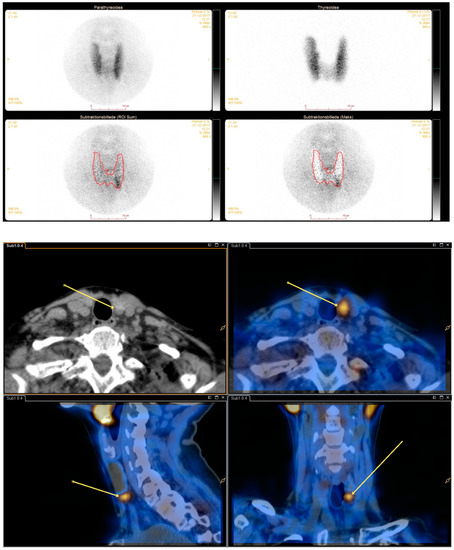

See Figure 1 and Figure 2 for dual/dual and dual/single images.

Figure 1. Dual isotope planar pinhole subtraction scintigraphy and dual isotope subtraction single-photon emission computed tomography/computed tomography (SPECT/CT) images. (top image) Upper left: Tc-99m-sestamibi pinhole. Upper right: I-123 pinhole. Middle left and right: Varying degrees of subtraction. (bottom image) Dual isotope subtraction SPECT/CT with and without fusion.